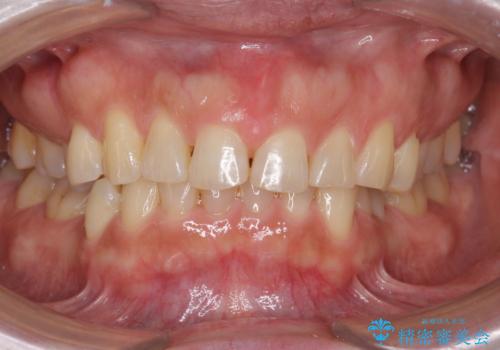

【インビザライン】八重歯が気になる

出っ歯をしっかり引っ込めたい

50代女性 部分矯正で 前歯の見た目改善 気になるところだけ